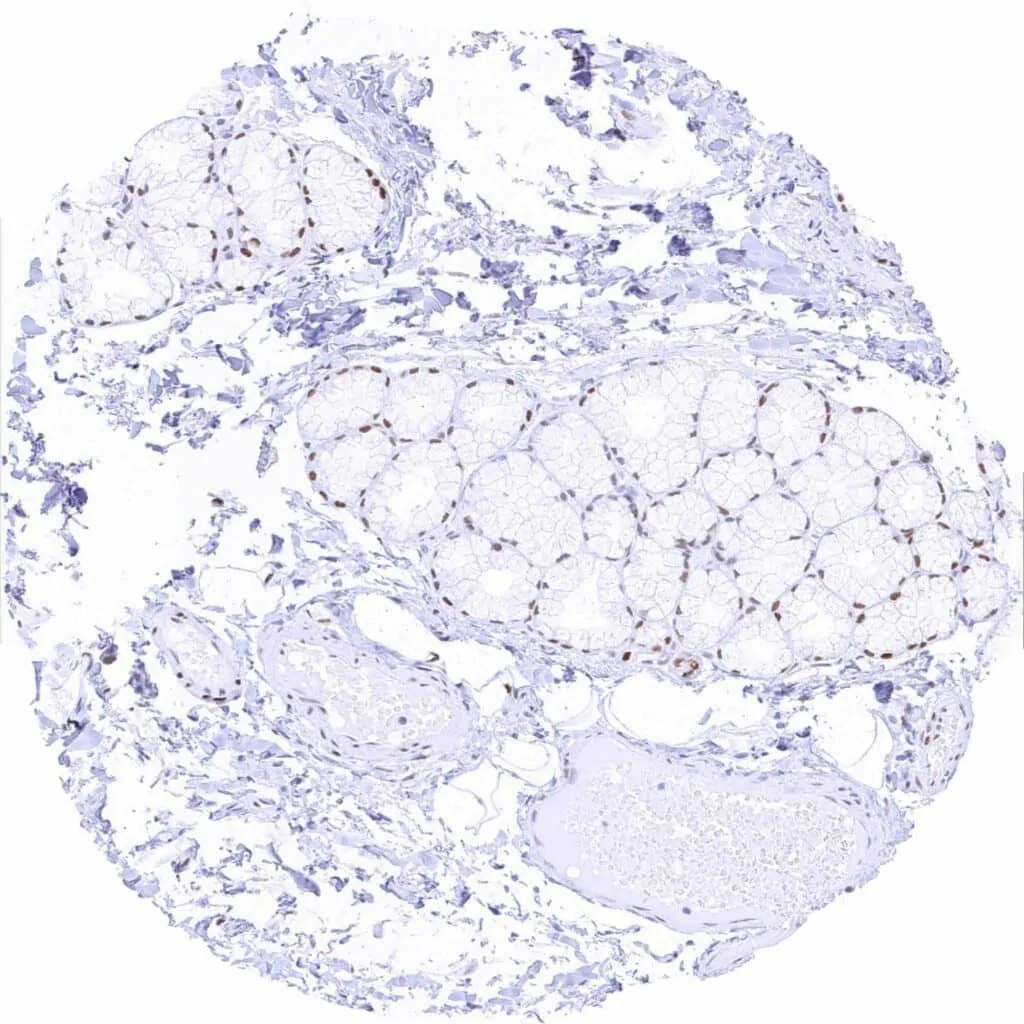

Fat

Lung – Weak to moderate TLE1 staining of mostly vascular cells

Thyroid gland – Weak TLE1 staining of follicular and endothelial cells